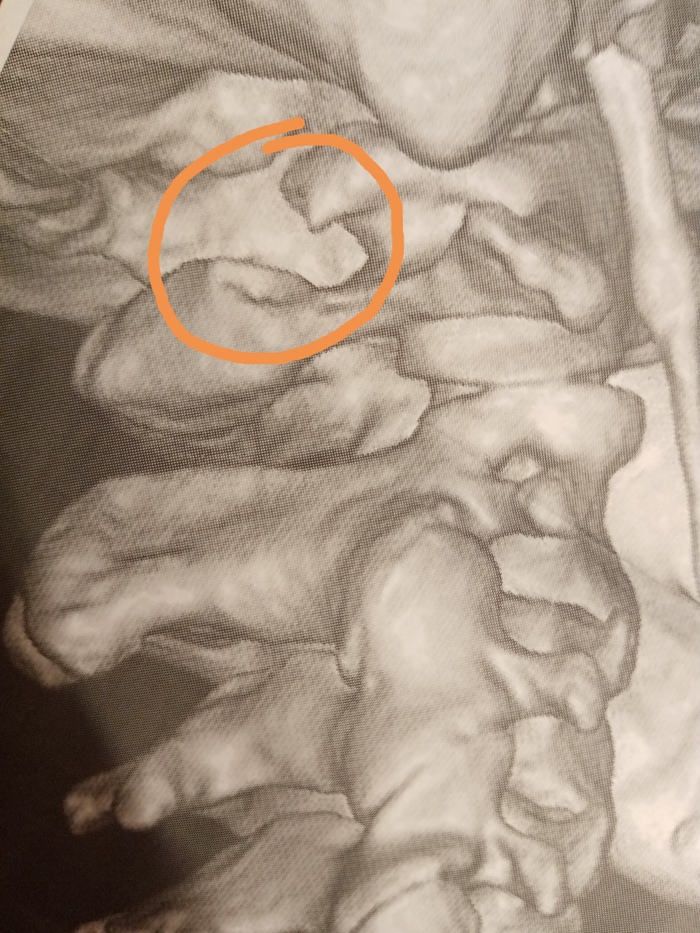

Невролог собрался отпускать домой с миром. Тут я вспомнила про шею! Напросилась сделать мне хотя бы рентген. И тут понеслось... Рентген выявил полное кольцо с левой стороны и полукольцо справа на первом шейном позвонке (Аномалия Киммерле). Ну, я-то знала - сужение есть, но никто тогда не сказал, что тенденция к полному зарастанию канала, и что этому есть научное название. По итогу рентгена невролог сказал сделать КТ с контрастов, чтоб посмотреть проходимость шейных вен. Как оказалось, слева всего лишь нитеподоный кровоток. Короче, почти нет сообщения с головой.

Дмитрий Владимирович спокойно всё объяснил, показал на снимках, рассказал о последствиях отказа от операции. Было страшно, но я понимала, что так, как жила эти 10 лет, жить нельзя. Надо соглашаться.